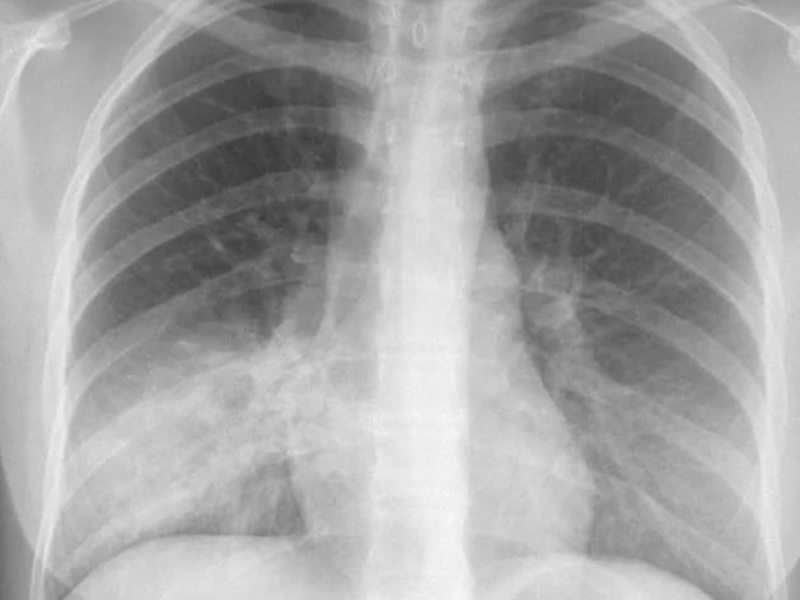

После проведения рентгенографии снимки должен изучить специалист, и на основе полученных данных и результатов других исследований сделать соответствующие выводы и поставить диагноз. В норме легкие и бронхи человека выглядят следующим образом:

- легочные доли имеют одинаковый, равномерный черный оттенок;

- в районе сердца наблюдается белый просвет;

- ребра и ключицы серые, с привычными очертаниями;

- купола диафрагмы белого цвета;

- позвоночный столб расположен в центре.

Важным этапом постановки диагноза остаётся отличие её от других заболеваний лёгких, коронавируса. Так, при бронхите будет отсутствовать затемнение на снимке, вместо этого — усиление лёгочного рисунка.

Усиление лёгочного рисунка